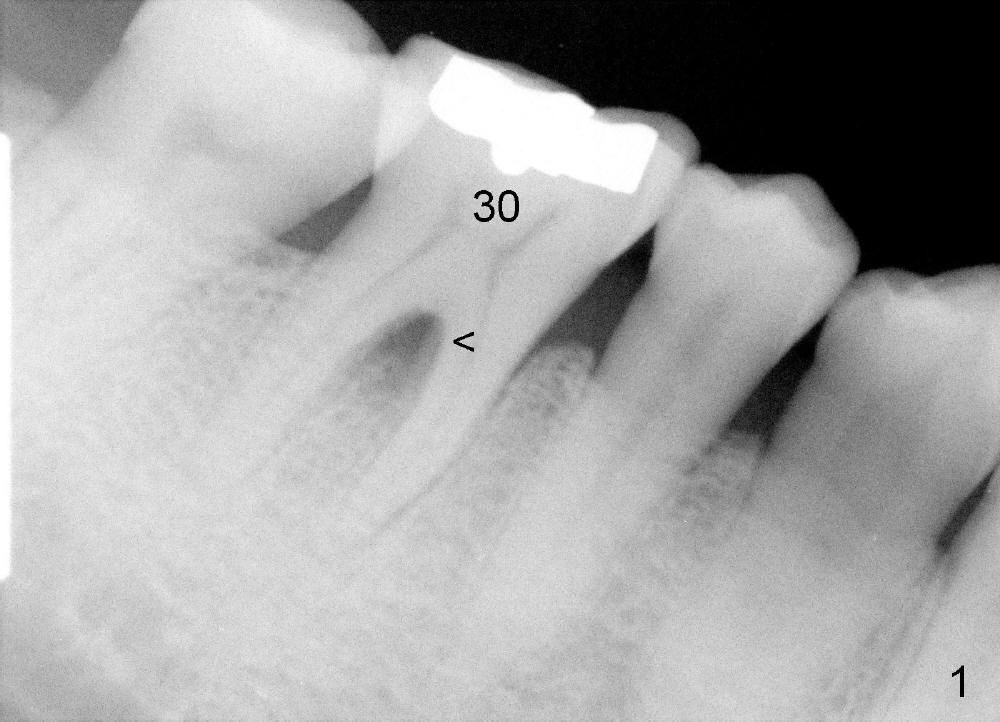

A 47-year-old man has had perio infection in the lower right 1st molar twice (Fig.1,2). Buccal and lingual furca pockets are ~ 9 mm. Following extraction and sectioning the septum, the osteotomy is initiated with a 2 mm pilot drill (Fig.3). Although the drill deviates into the mesial socket, the coronal end is controlled more or less in the middle of the edentulous area (compare white and red lines). Ideally the axis of the osteotomy (Fig.4 red line) should be parallel to that of the 2nd molar and perpendicular to the curve of Spree. The coronal end of the 3.5 mm reamer (Fig.5) and of the 7x17 mm tap (Fig.6 T) remains in the center of the edentulous space. The apical threads of the tap are engaged into the bone for stability (Fig.6 <). When 7x17 mm implant is placed with > 60 Ncm, the mesial socket is obliterated while the density of the distal one increases because of autogenous bone grafting (Fig.7*).